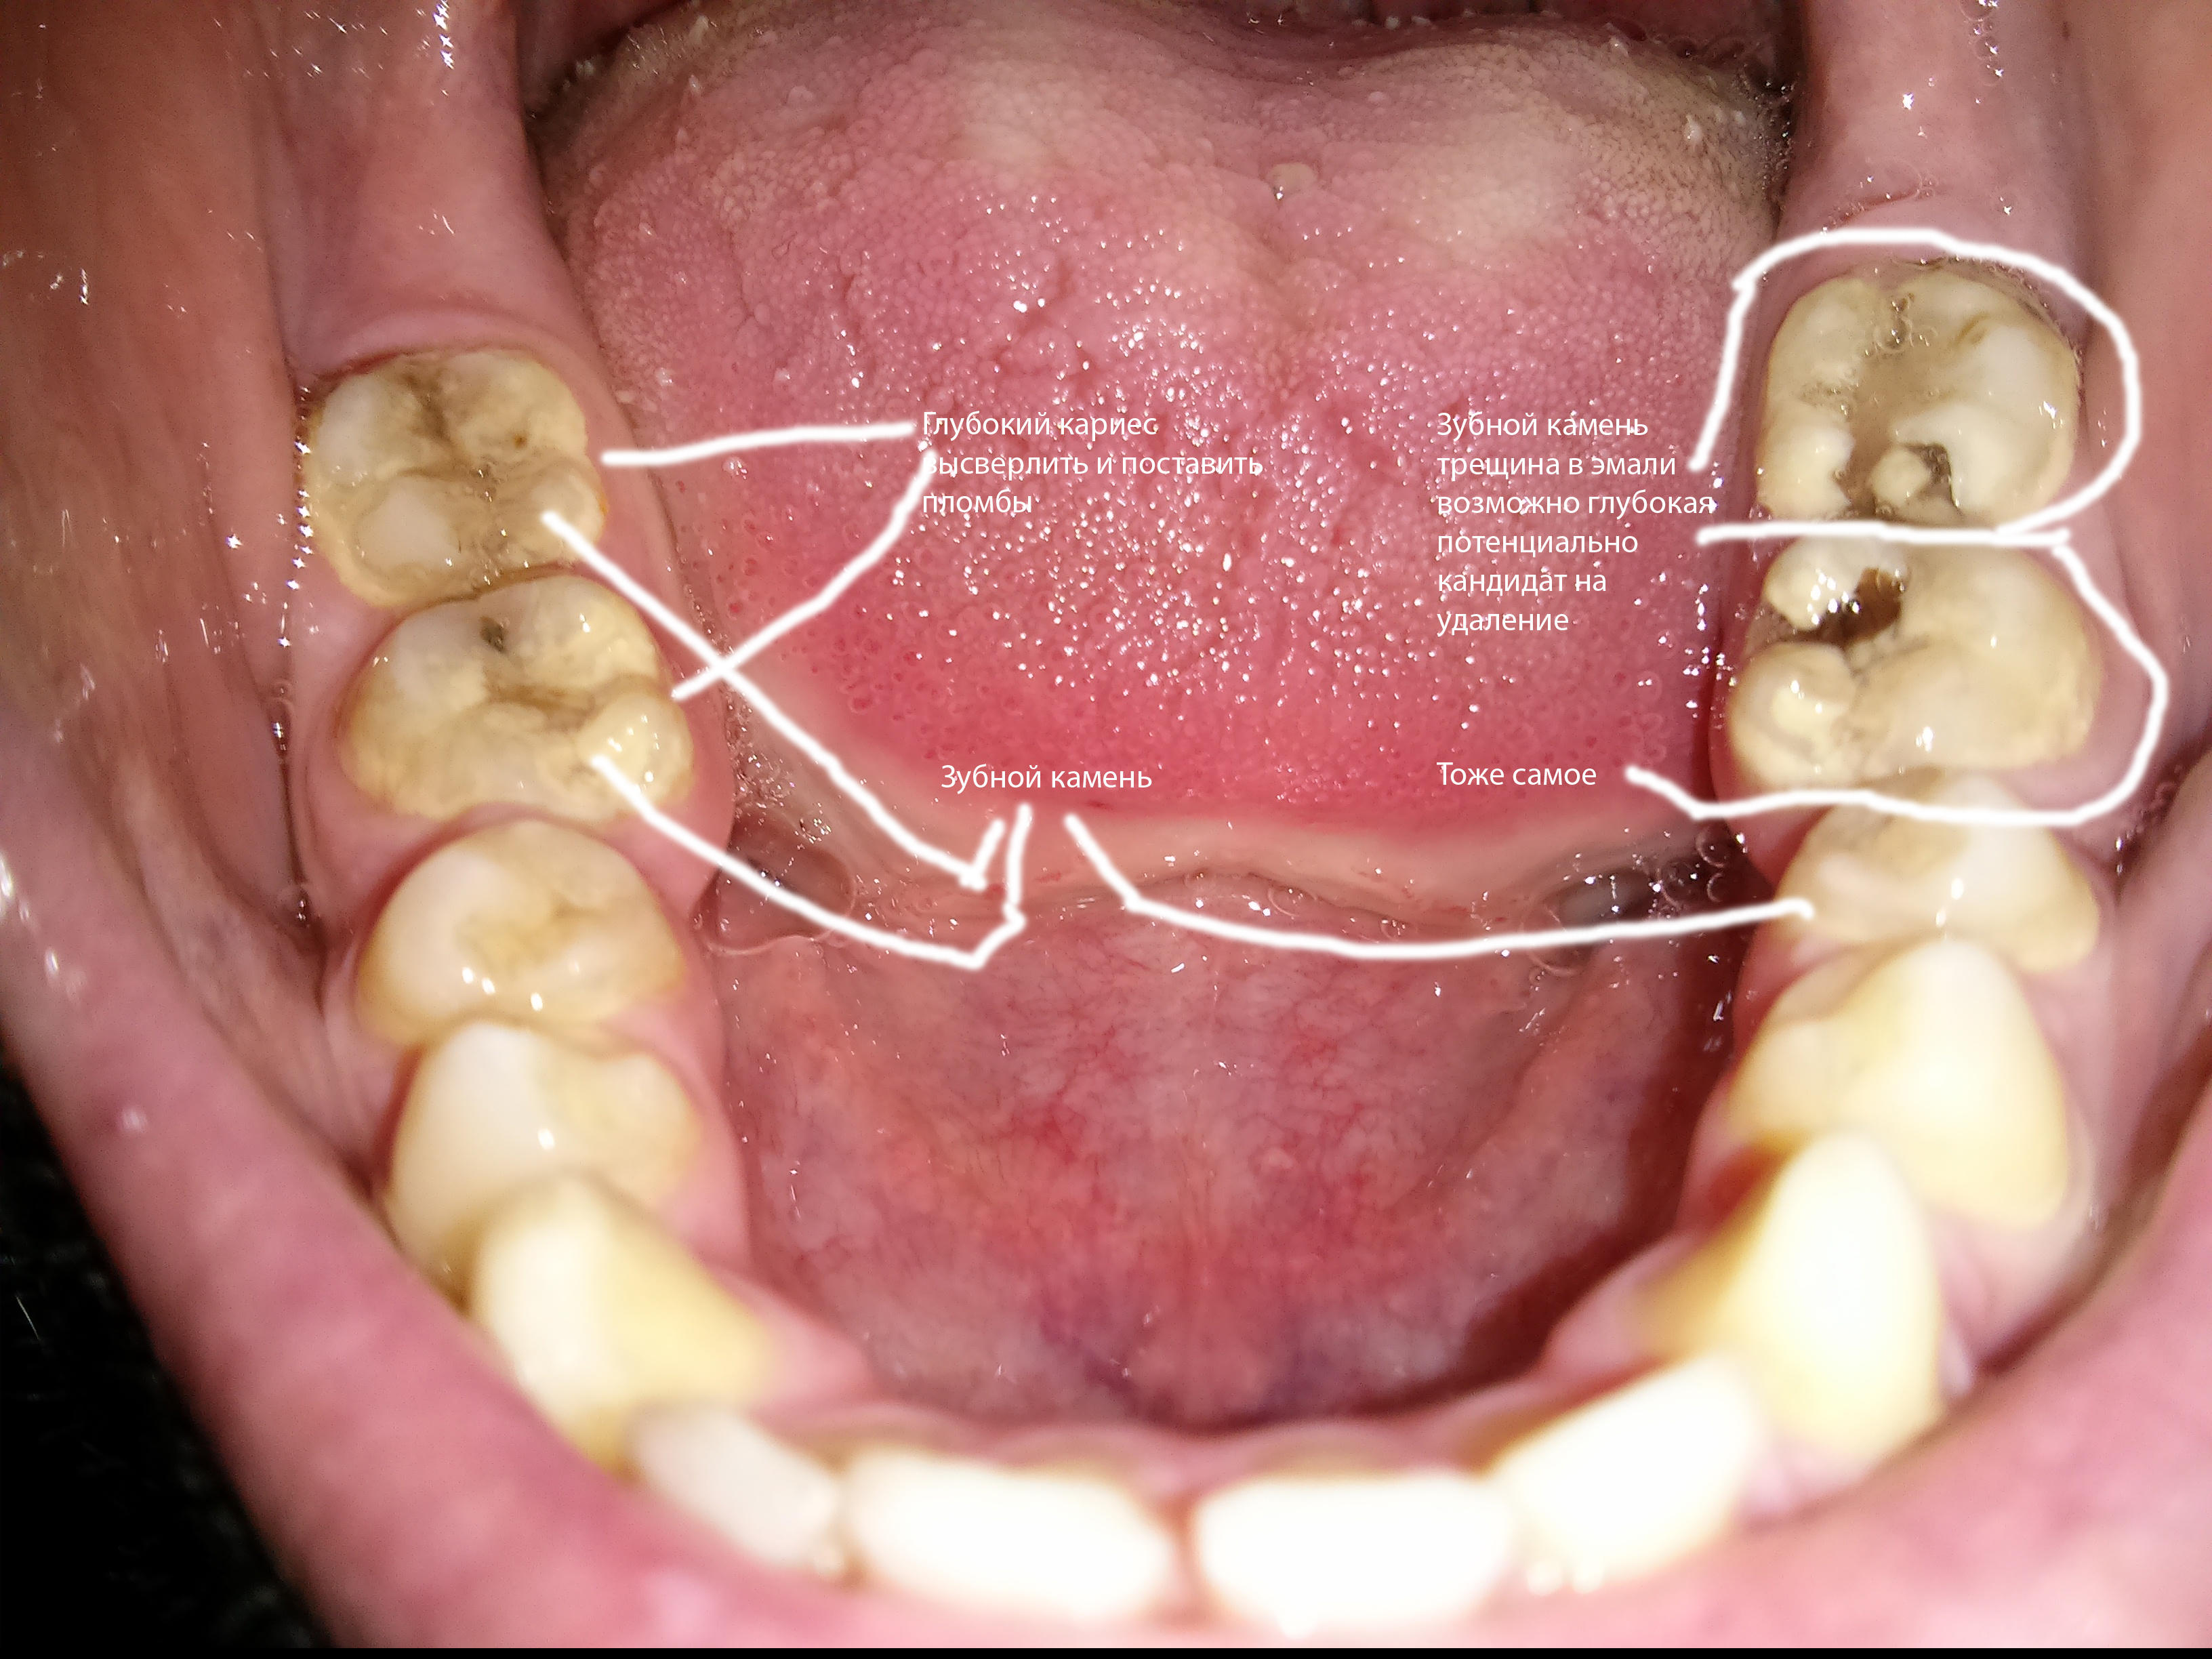

1395175059731.jpg

Мыльновато.

>dat two krivie zybi

>>64593224

О, эту королевскую желтизну не скроет никакое мыло, уважаю.

Прозвучало как оскорбление.

1395175377727.jpg

Мои нижние.

ОП-хуй.

Аноним Срд 19 Мар 2014 00:46:36  #24 №64593769

>>64593557